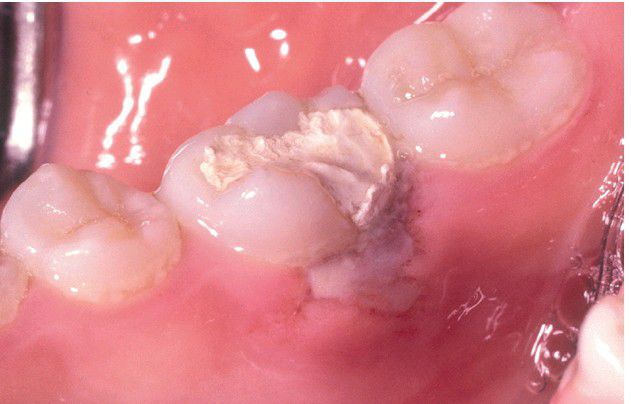

Formocresol Burn.

Tissue necrosis secondary to leakage of endodontic material between a rubber dam clamp and the tooth.